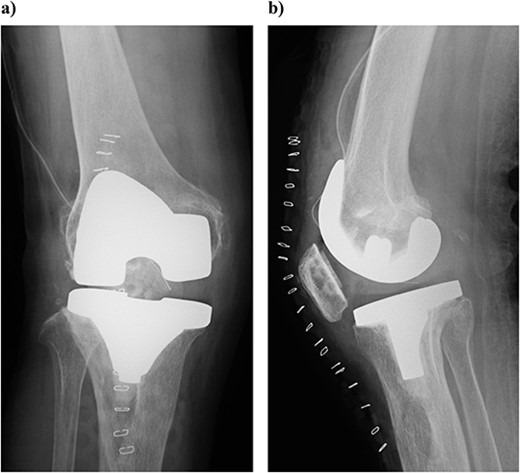

On physical examination, the patient extension and flexion were − 20° and 130°. A defect of the tibial tubercle was observed. The Knee Society (KS) score was 44 points, and the Knee Society function (KS-F) score was 70 points. A plain radiography showed valgus knee osteoarthritis assessed as Kellgren–Lawrence grade 4. In addition, a well-defined translucent image of bone appeared near the central part of the proximal tibia and no tibial tubercle could be observed (Fig. 1). Magnetic resonance imaging (MRI) of the right knee joint showed the patellar tendon appeared from the attachment on the patella with continuity to the tibial bone marrow in T1- and T2-weighted imaging (Fig. 2).

Plain radiography at the patient’s first visit: (a) standing front, (b) lateral side and (c) thigh, standing, front, full length. Valgus knee osteoarthritis and well-defined osteoporosis near the central part of the proximal tibia can be seen, and the rough surface of the tibia has been worn away.